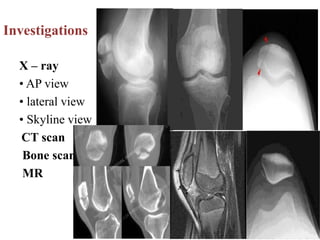

Investigations

X – ray

• AP view

• lateral view

• Skyline view

CT scan

Bone scan

MR